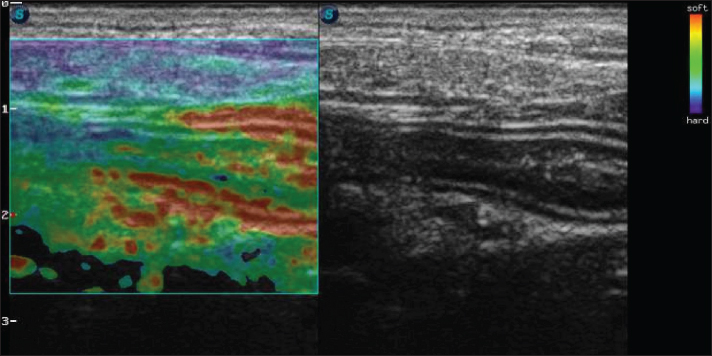

Strain elastography was performed using the same ultrasound machine with a linear transducer and a frequency of 10 MHz. The transducer was positioned on the animal’s abdomen, and then, five cycles of compression and decompression were performed. The color histogram was generated and superimposed on the duplicate B-mode image. This map generated images with a colorimetric scale ranging from blue to red for tissues with maximum stiffness, intermediate elasticity, and maximum elasticity.

For the static qualitative assessment, the proximal segments of the duodenum and jejunum were analyzed in a longitudinal ultrasound section, and a heterogeneous distribution was found between the dorsal and ventral regions of the intestine, with patterns ranging from predominantly blue with some greenish parts and reddish foci (Fig. 2). To obtain the semiquantitative parameters, the region of interest (ROI) was drawn using the device’s software cursor. Initially, a reference, ROI 1 was obtained in the mesentery adjacent to the intestines, and ROI 2 was drawn in the dorsal region of the duodenum and jejunum. The drawings were similar and circular with the same depth and horizontal direction in the cross-section. The drawings were based on the diameter of the animal’s intestinal mucosa, and the force applied was guided by the elastographic compression wave. The strain ratio (SR) was obtained by calculating the ratio between the ROIs. The values for the duodenum were as follows: ROI 1=1.04 % and ROI=0.4%, with an SR of 2.58 (Fig. 3A). In the jejunum, ROI 1 measured 1.46 %, ROI 0.74 %, and SR 1.97 (Fig. 3B).

Fig. 2. Color elastography in double projection with a B-mode ultrasound image of a longitudinal scan of the proximal jejunum. The submucosa, muscularis, ventral, and dorsal serosa are red-green; the ventral and dorsal mucosa are blue-green.